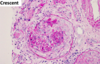

Wilms tumor Microscopic features (3)

- Triphasic pattern*

- Primitive blastema (small/dark undifferentiated cells)

- Epithelial component (abortive tubules/glomeruli)

- Stroma (Fibrous or myxoid patterns; may contain mesenchymal elements (cartilage, muscle, bone)

Wilms tumor microscopic features (3):

Triphasic pattern

- Primitive blastema (small/dark undifferentiated cells)

- Epithelial component (abortive tubules/glomeruli)

- Stroma (Fibrous or myxoid patterns; may contain mesenchymal elements (cartilage, muscle, bone)

ANAPLASIA

Determines the Prognosis of Wilms tumor

- Pleomorphism, hyperchromatism, abnormal mitoses –> more aggresssive; higher resistance to chemotherapy